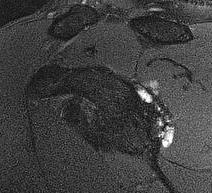

MRI

Spinoglenoid cyst

Spinoglenoid cyst with SLAP tear and posterosuperior labral tear